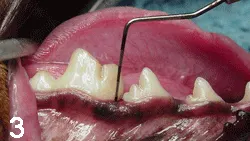

Local tissue may appear normal despite underlying disease, defining the need for periodontal probing and radiography (Figures 3-5).

Figure 3: No obvious evidence of periodontal disease is present in this patient.

Figure 4: Radiograph of the right mandible of the patient in Figure 3. Bone loss is evident surrounding the roots of the fourth premolar. The patient was observably more active after surgery to correct the defect.